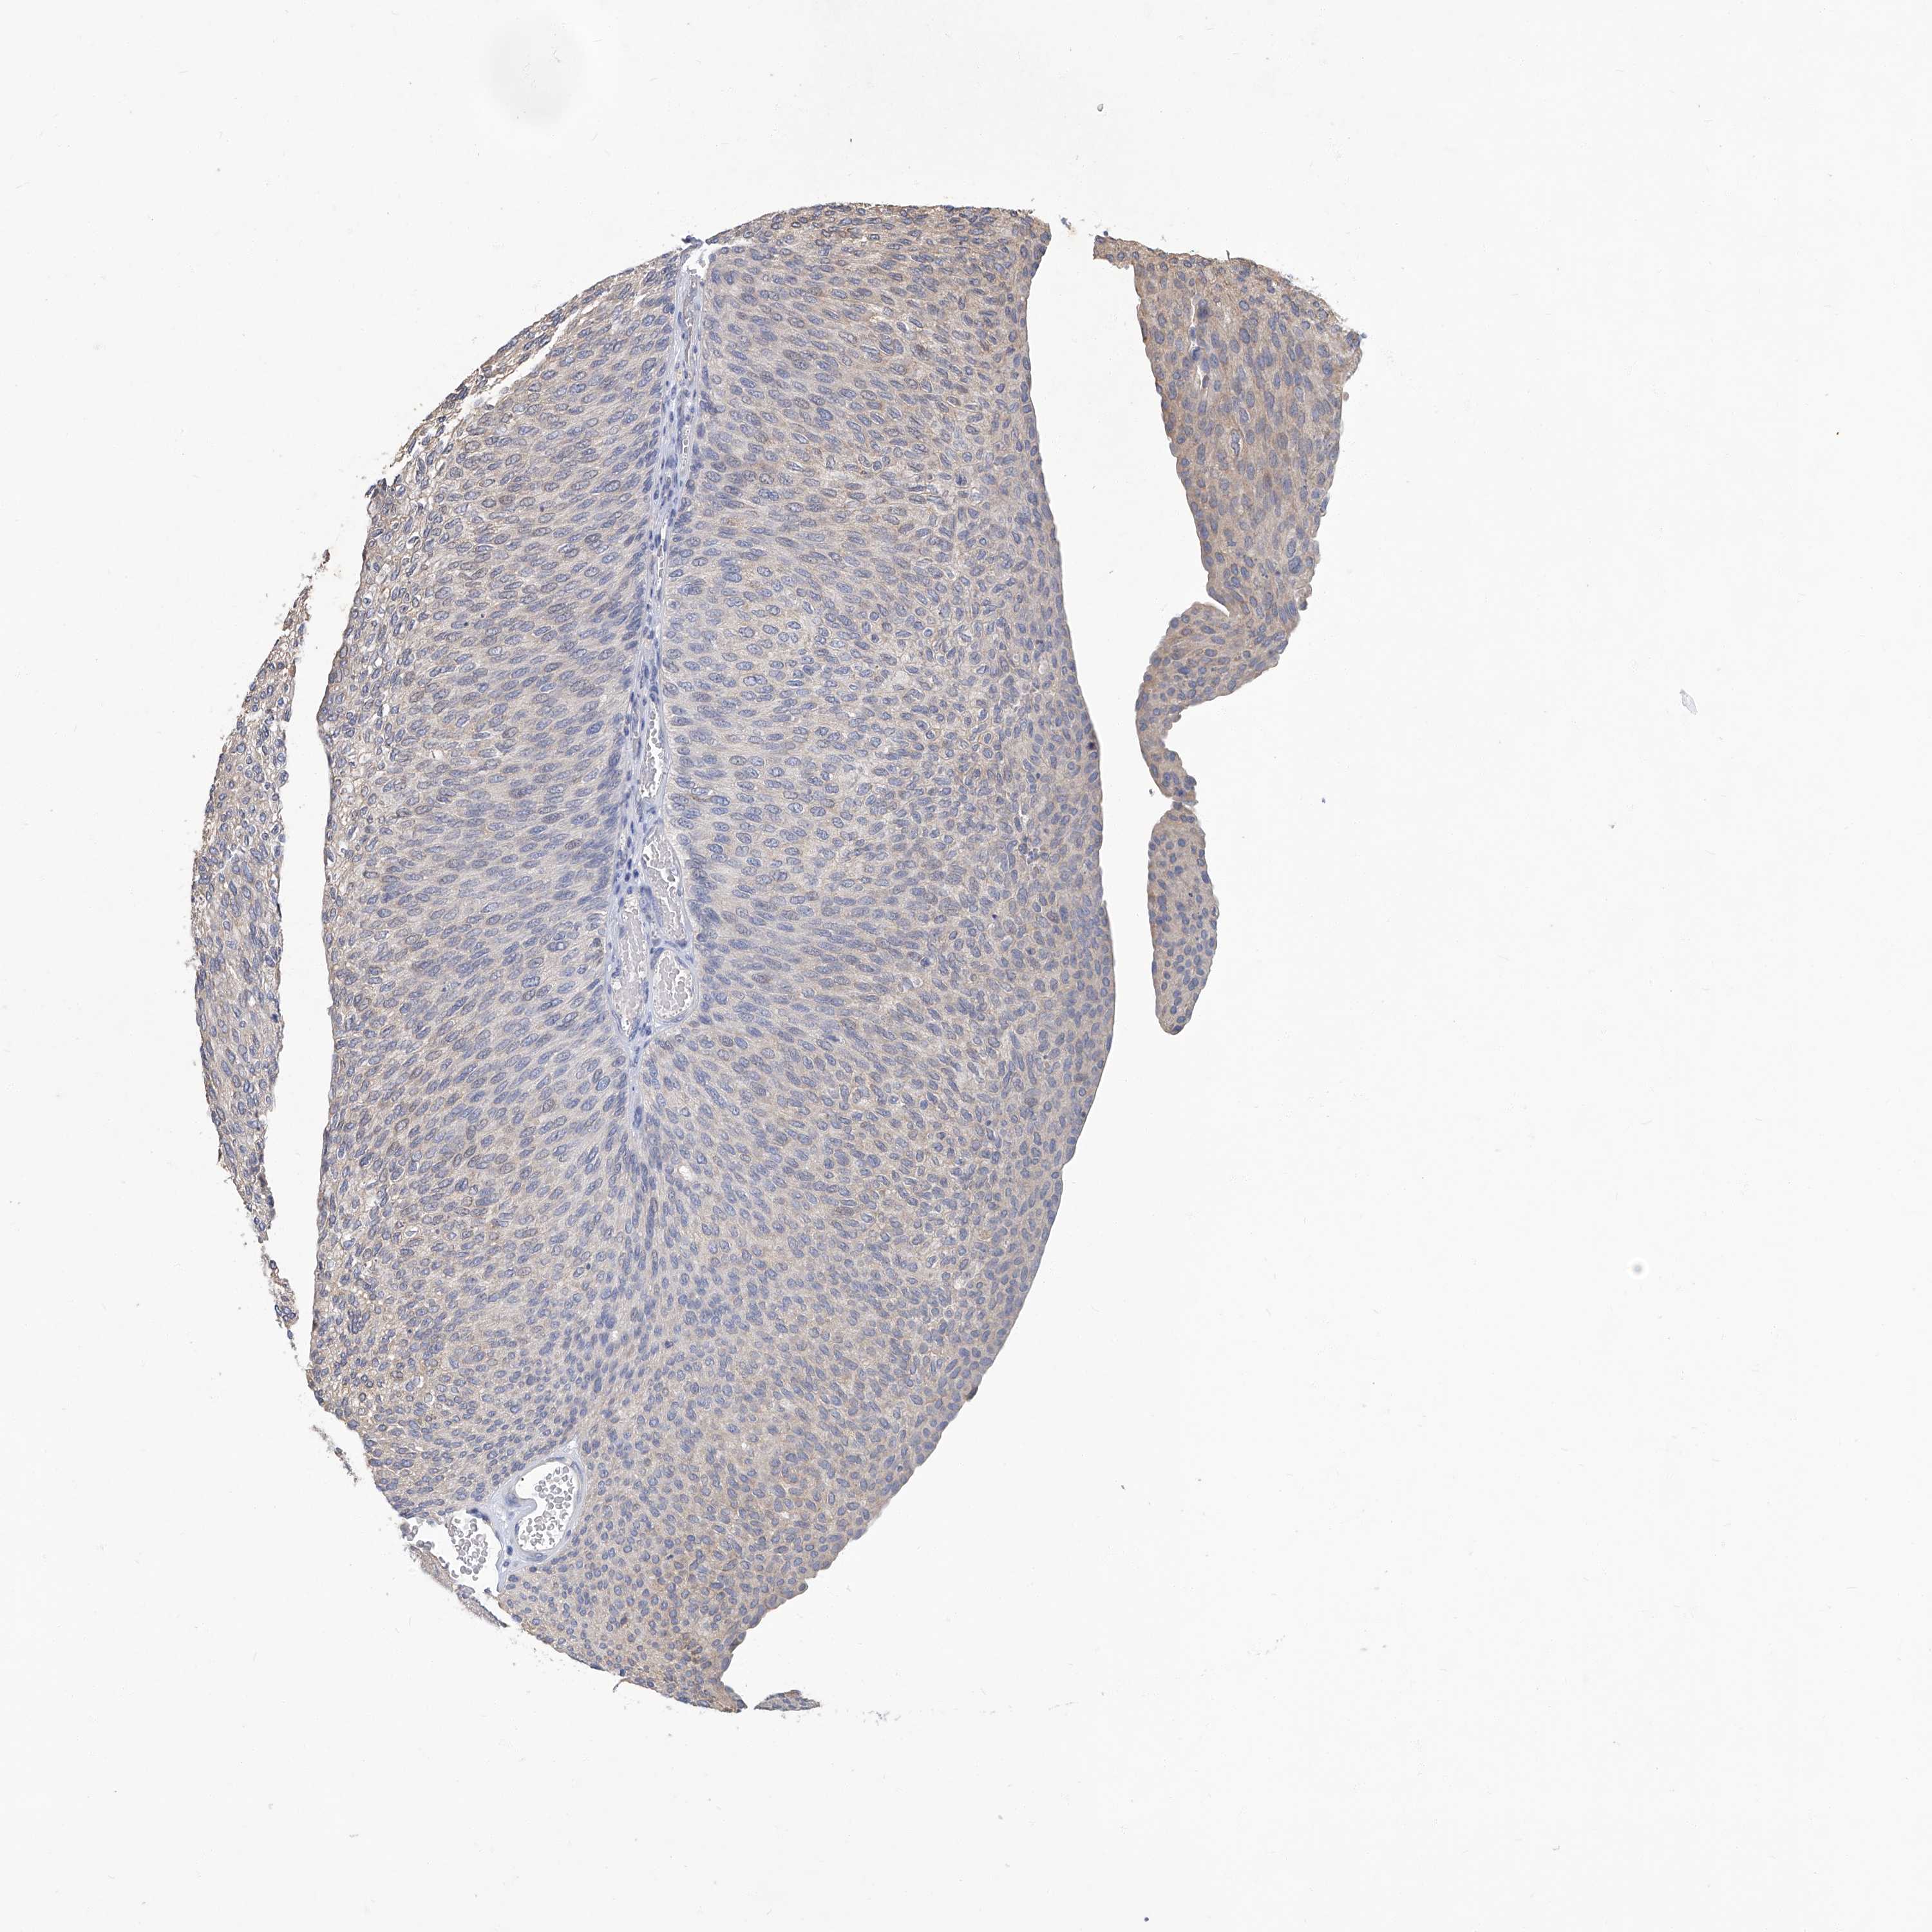

UROTHELIAL CANCER - Protein expressioni

A mouse-over function shows sample information and annotation data. Click on an image to view it in a full screen mode. Samples can be filtered based on level of antibody staining by selecting one or several of the following categories: high, medium, low and not detected. The assay and annotation is described here.

Note that samples used for immunohistochemistry by the Human Protein Atlas do not correspond to samples in the TCGA dataset.

Antibody stainingi

Antibody staining in the annotated cell types in the current human tissue is reported as not detected, low, medium, or high, based on conventional immunohistochemistry profiling in selected tissues. This score is based on the combination of the staining intensity and fraction of stained cells.

Each image is clickable and will lead to virtual microscopy that enables deeper exploration of all samples and also displays staining intensity scores, fraction scores and subcellular localization as well as patient and tissue information for each sample.

Antibody CAB002441

Antibody CAB031481

Staining

High

Medium

Low

Not detected

Intensity

Strong

Moderate

Weak

Negative

Quantity

>75%

75%-25%

<25%

None

Location

Nuclear

Cytoplasmic/membranous

Cytoplasmic/membranous,nuclear

Urothelial carcinoma, High grade

Urothelial carcinoma, Low grade

Adenocarcinoma, NOS